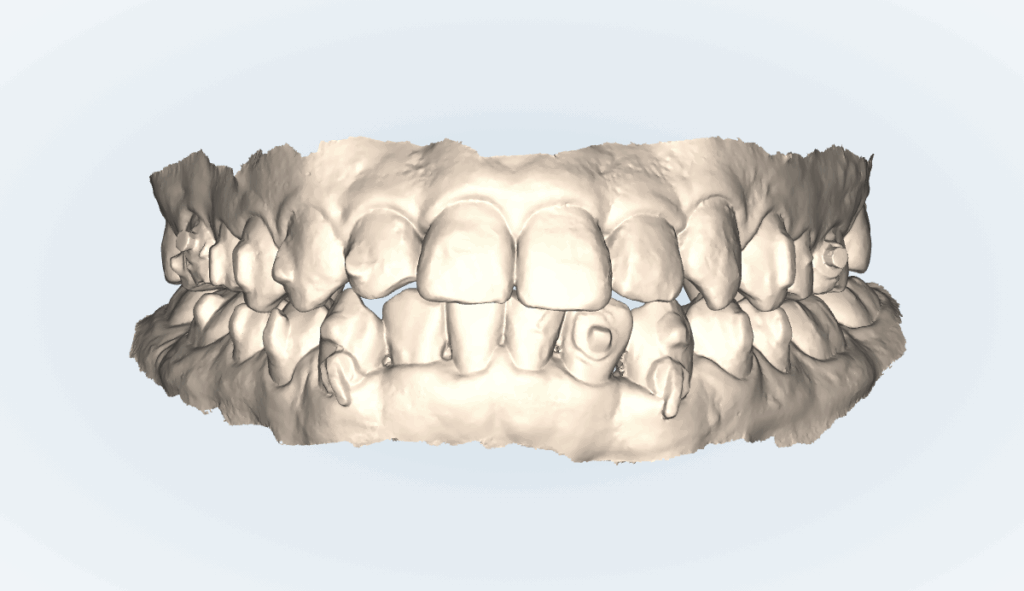

インビザライン矯正治療。59ステージ。治療費554,400円+調整料(初回)16,500円+調整料5,500円×回数+リテーナー55,000円。

1日20時間以上装着、1ステージ10日間。つまり590日、約20ヶ月。約1年8ヶ月の計画です。

最初がこんな感じですから患者さんの満足してくれていますので、積極的な治療を終えて良くなった歯並びを保つためにリテーナーを装着してもらうことにしました。

「もっとこうしたい」がないわけではないのですが、患者さんが満足しているので積極的にはを動かすのは終了させて、この状態を保つことにしました。